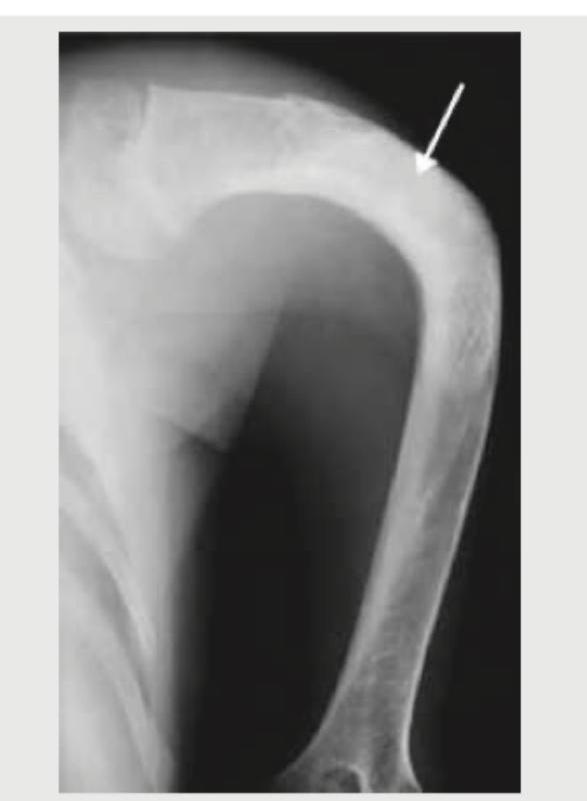

The given X-ray of the humerus shows:

Explanation: ***Fibrous dysplasia*** - The image shows a humeral lesion with a **ground-glass matrix** and areas of **cortical thinning** and expansion, consistent with fibrous dysplasia. - Fibrous dysplasia is a developmental anomaly where normal bone is replaced by **fibrous tissue** and immature woven bone, often appearing as a **shepherd's crook deformity** in long bones. *Aneurysmal bone cyst* - Aneurysmal bone cysts typically present as expansile **lytic lesions** with multiple **fluid-fluid levels** on imaging, which cannot be clearly discerned on this X-ray. - While they can be expansile like the lesion shown, they characteristically have a **"soap bubble" appearance** due to internal septations. *Ewing sarcoma* - Ewing sarcoma often presents with a destructive, infiltrative lesion and a characteristic **"onion-skin" periosteal reaction**, none of which are definitively seen here. - This highly malignant tumor typically causes **moth-eaten or permeative bone destruction**, which is distinct from the more uniform ground-glass appearance. *Posterior dislocation of shoulder* - A posterior dislocation of the shoulder would show the **humeral head displaced posteriorly** relative to the glenoid, often characterized by a "light bulb" sign or loss of true glenohumeral articulation. - The image exhibits an **intramedullary lesion** within the humeral shaft, not a displacement of the joint.